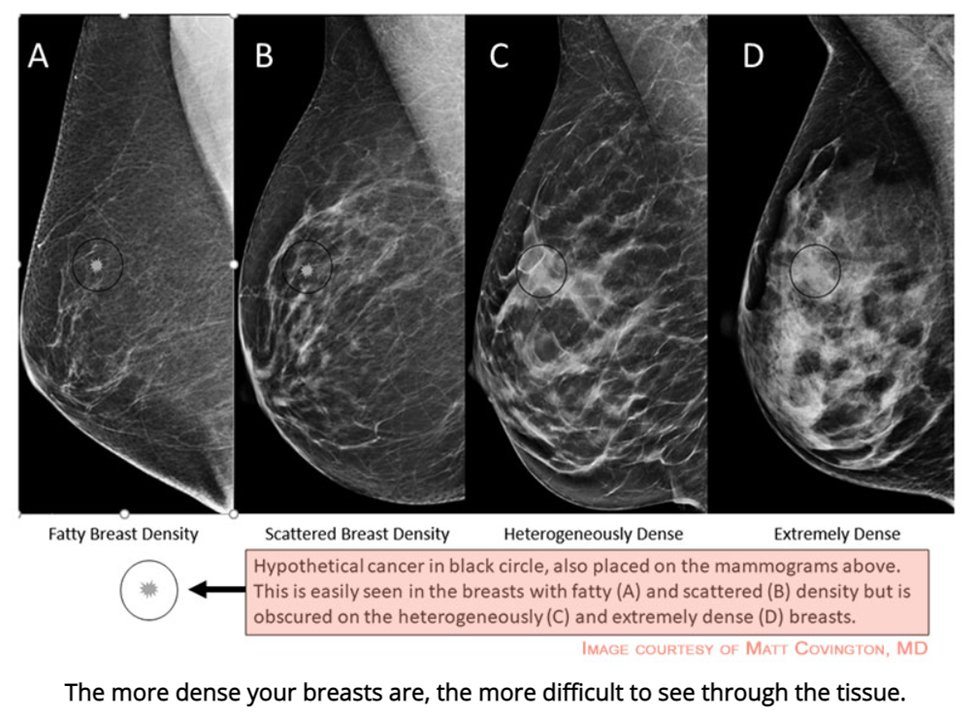

Matt Covington Md Mfcovington Twitter